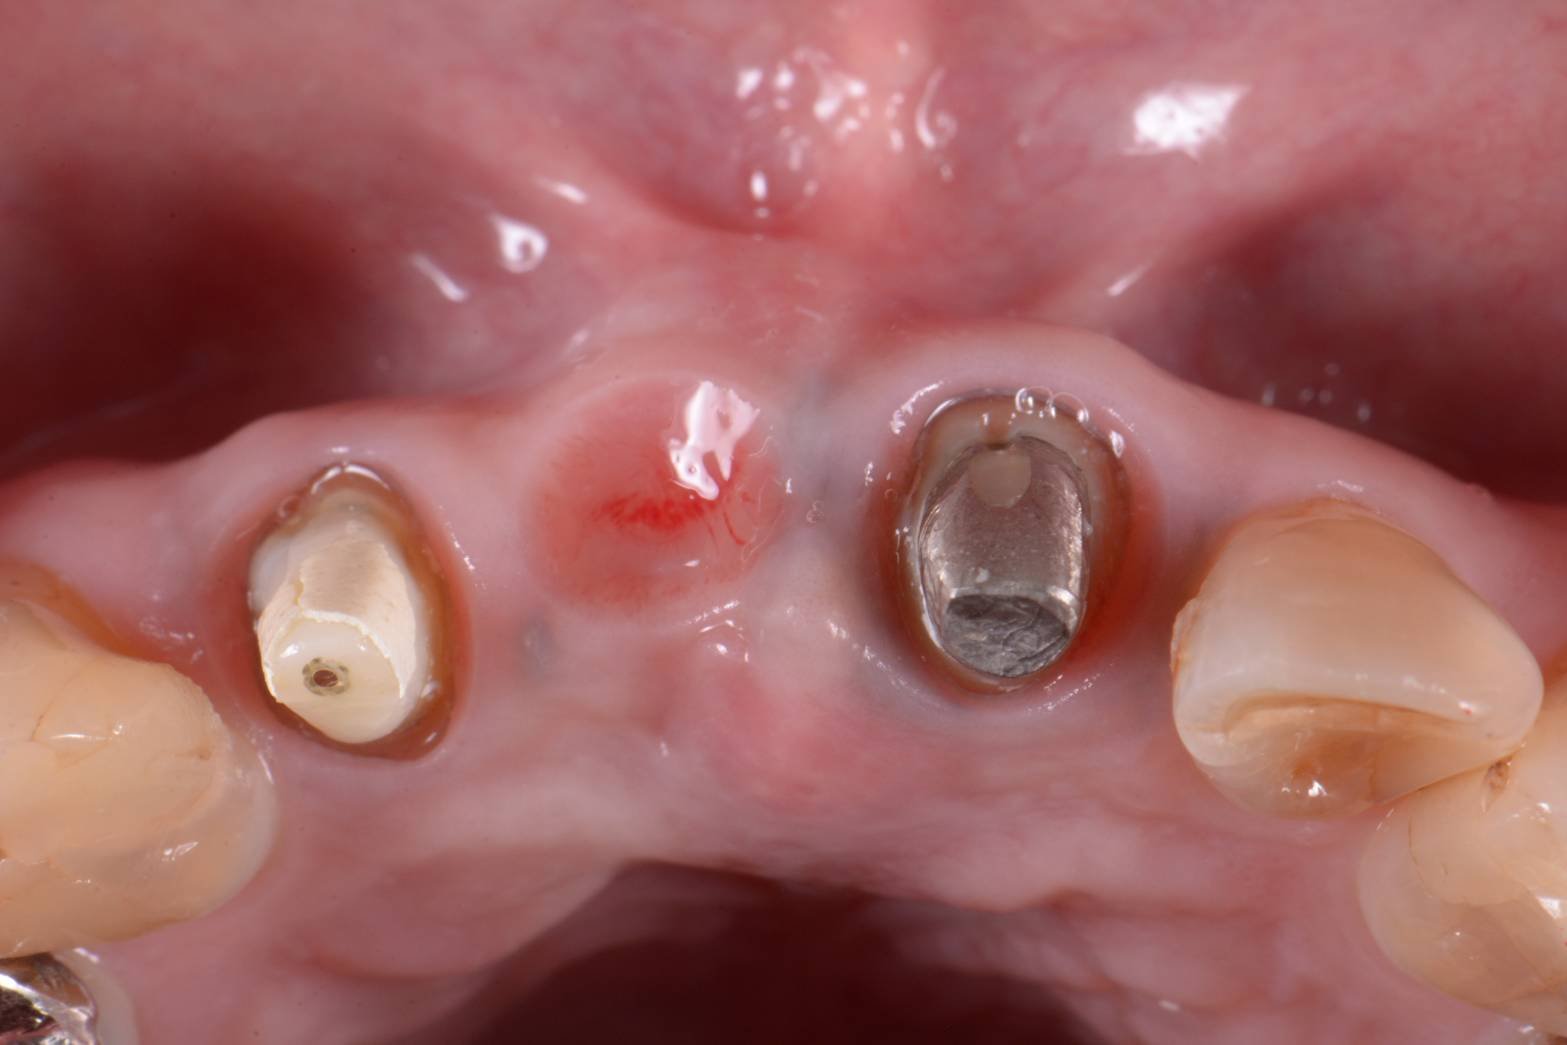

さらにこのオベイドポンティックを造るためには、歯肉の移植も必要なのです。↓の写真